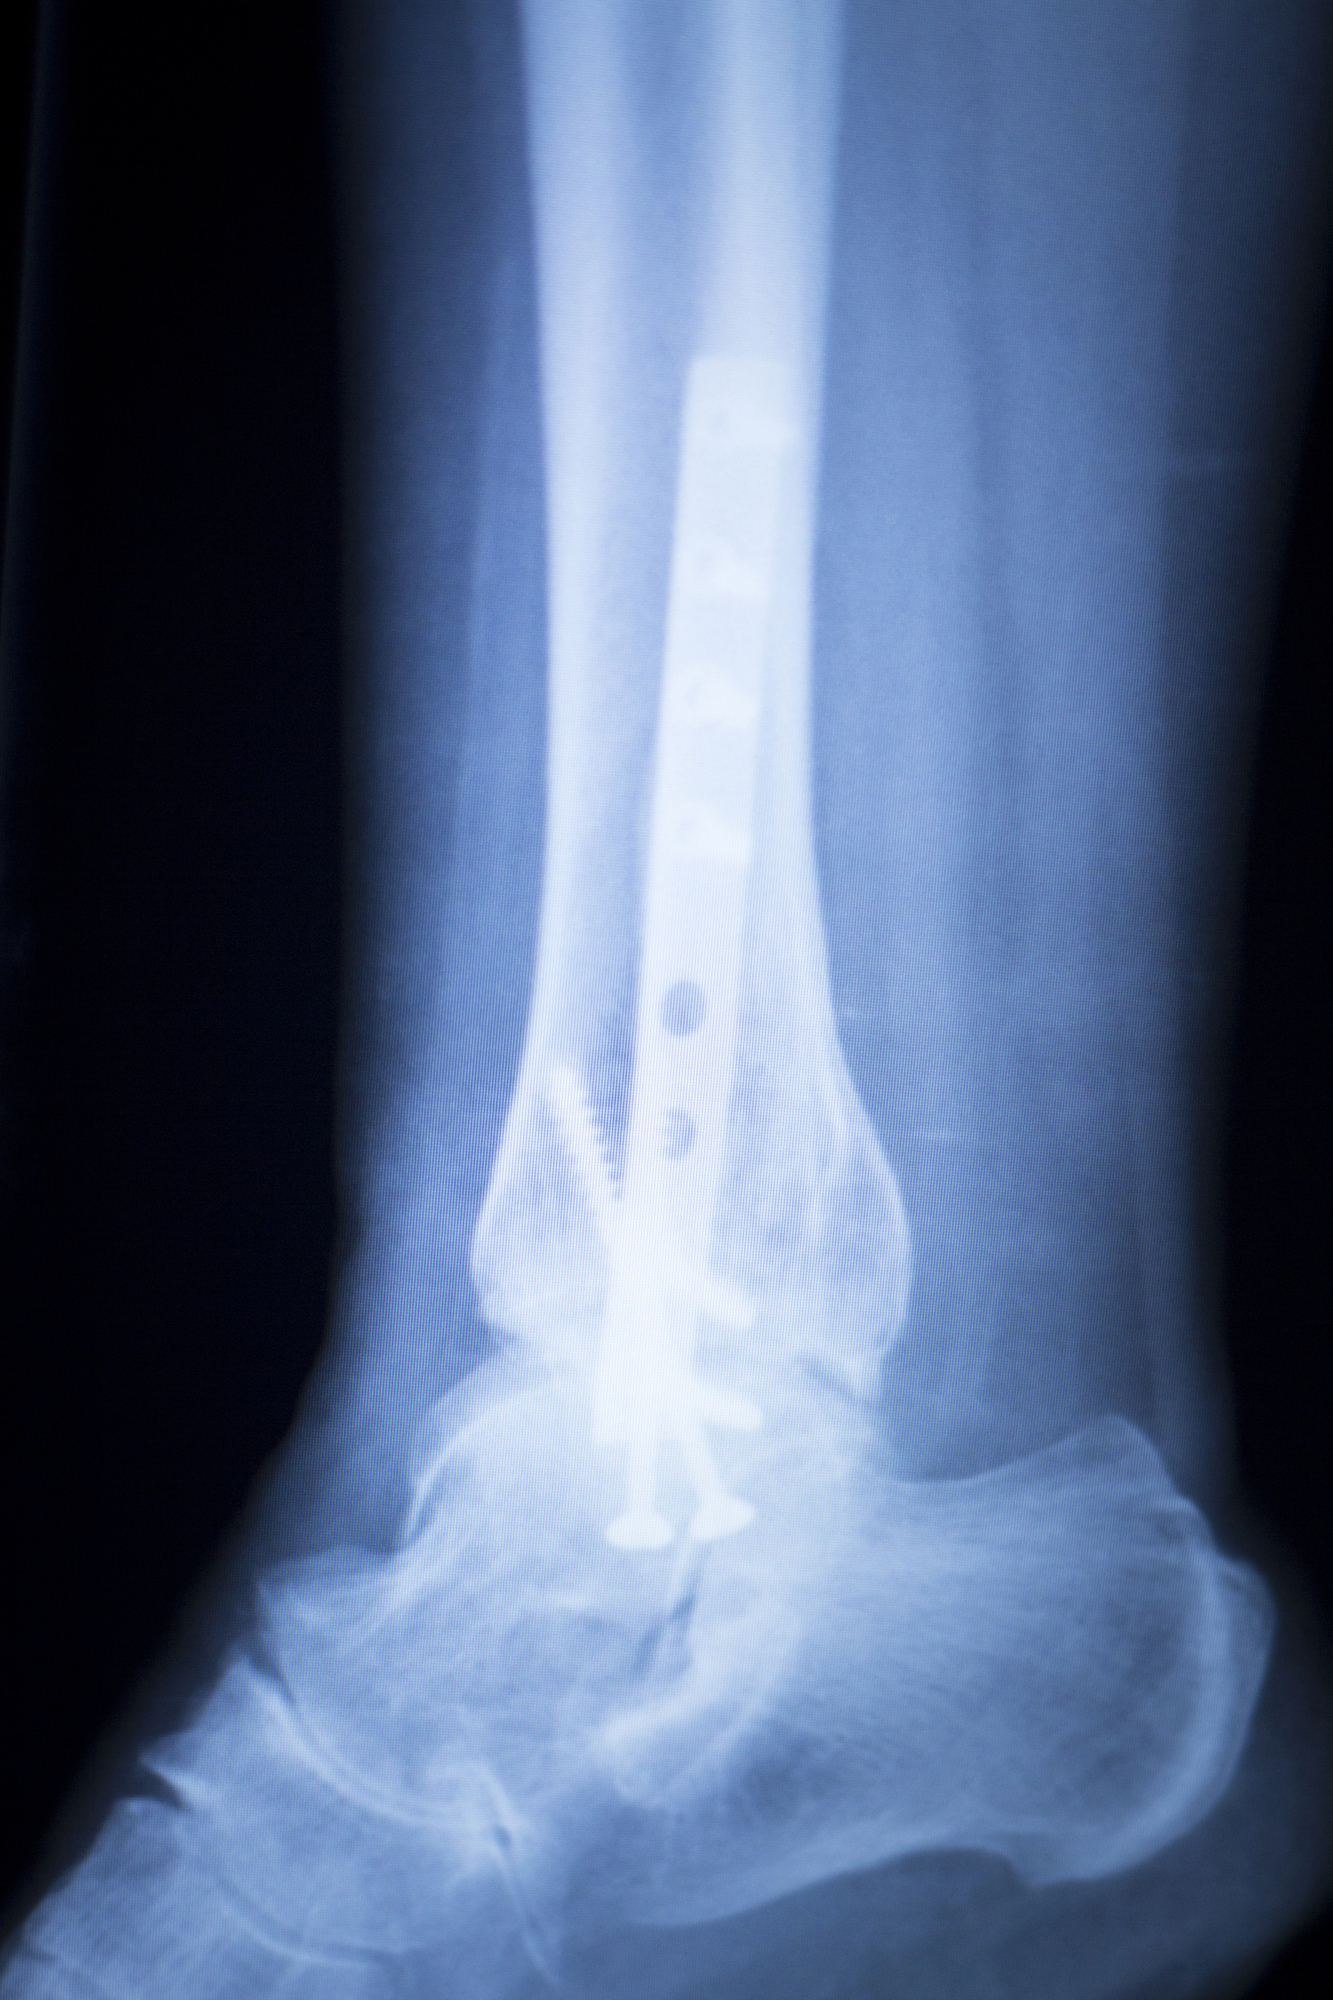

Research on surgery for advanced ankle osteoarthritis

Marc Darrow, MD. JD. A recent study (1) discusses the problem orthopedists and surgeons have in presenting treatment options to their patients with advanced ankle osteoarthritis. As many doctors and patients are aware, ankle osteoarthritis treatment protocols have no real guideline recommendations of its own. Researchers say most doctors treat an ankle problem as they … Continue reading Research on surgery for advanced ankle osteoarthritis